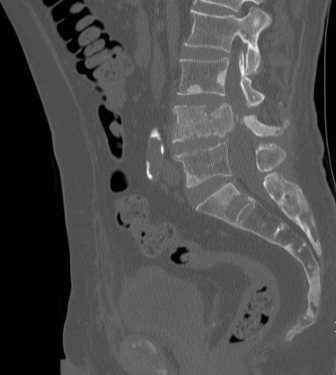

Entre temps l’examen suivant a pu être réalisé :

Question 13 : Vos envisagez le (ou les) diagnostic(s) de :

Scanner pathologique avec recul du mur postérieur de L4 associé à des lésions ostéocondensantes, en contexte d’ascension du PSA. Ce tableau est typique d’une complication osseuse du cancer de prostate.

L’absence de signe neurologique exclut les diagnostics de compression de la queue de cheval, et de compression médullaire, ce dernier étant improbable compte tenu de la localisation du syndrome rachidien (L4).

À noter cependant que l’hormonothérapie des cancers de prostate est un facteur de risque d’ostéoporose.